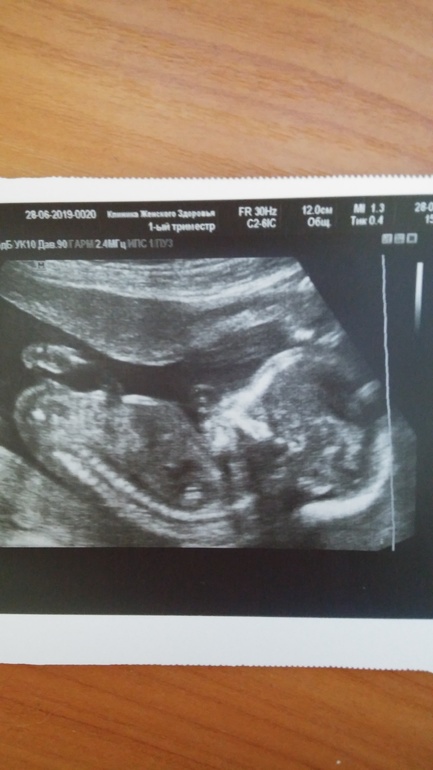

Ну вот и сходили на 2 узи,не дотерпела до 20 недель,переживала очень...низкую плацентацию ставили.Теперь сказали всё хорошо у нас,плацента немного поднялась и ещё поднимется.И шевелений не чувствовала совсем,а вот в пятницу ,наконец то ощутила😘...Я думаю вы поймёте,как это трогательно и волшебно,испытать это после стольких лет мучений и слёз,поэтому не буду описывать...Токсикоз отступил,только тахикардия меня не оставляет,сердце колотится почти со скоростью моего малыша,не отстаёт.Грудь по прежнему болит не утихает....Второй раз,нам уже подтвердили доченьку,поэтому сомнений у меня уже совсем нет...А так вообщем всё у нас хорошо!!!